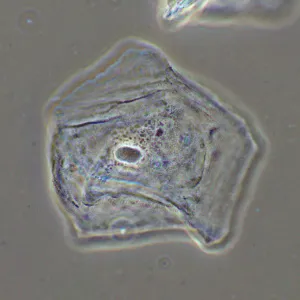

Фазово-контрастное устройство MAGUS SPH2 – это набор аксессуаров, которые позволяют реализовать на микроскопе MAGUS метод фазово-контрастной микроскопии. Фазовый контраст применяют для изучения прозрачных объектов, слабо различимых в светлом поле. Этот метод не требует окрашивания, повреждающего структуру живых образцов, поэтому подходит для широкого круга медицинских и фармакологических исследований.

ФКУ MAGUS SPH2 включает 2 слайдера фазового контраста, 4 планахроматических объектива с фазовыми кольцами, вспомогательный центрирующий телескоп.